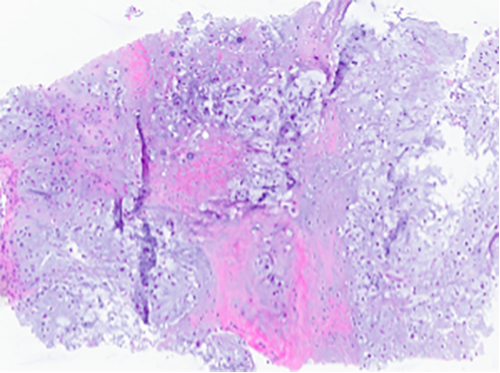

Imaging and Histology Microscopic Findings

Imaging (CT Neck with contrast) demonstrated a 3.4 x 3.2 x 3.5 cm hypoattenuating mass lesion centered on the right thyroid cartilage with associated destructive changes of the thyroid cartilage and scattered calcified the lateral margin of the mass extends into the strap muscles which are displaced anteriorly and laterally with probable invasion or extension of the mass lesion into the strap muscle body and with medial extension into the right para-glottic space and right aryepiglottic fold.

Histological analysis of the biopsy demonstrated a cartilaginous lesion with increase cellularity, diffuse growth and moderate atypia. No high grade features was appreciated, including pleomorphic appearance and easily identifiable mitotic figures.

H&E stain (100X)

H&E stain (400X)